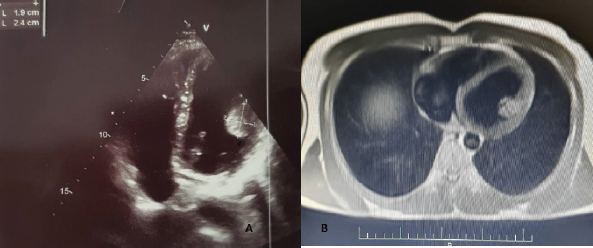

A 44-year-old rancher was referred to a neurologist with complaints of mood swings, restlessness, and headaches that worsened after lifting heavy weights. The patient did not have any significant illness in their previous history and did not complain of vomiting, weight loss, or fever in their new illness. The neurological examination did not show any findings in favor of cerebral palsy or focal neurological symptoms. A CT-scan of the brain revealed an abnormal low-density mass in the right frontoparietal lobe, leading to the diagnosis of a possible cyst or abscess (Fig. 1). Antibiotic treatment was started for the patient, but after eleven days, the patient’s symptoms did not improve and even worsened. After re-imaging, the neurologist recommended that the patient see a neurosurgeon. During pre-operative investigations, consultation with a cardiologist was requested. Echocardiography revealed a moving mass confined to the anterolateral papillary muscle in the patient’s heart, even though the patient had no complaints or symptoms of heart disease (Fig. 2). Although the patient had only presented with symptoms of central nervous system involvement at the beginning of their visit, their cardiac findings were diagnosed completely by chance (a cyst confined to the anterolateral papillary muscle without any cardiovascular symptoms). In abdominal imaging, one round cyst in the spleen and upper pole of the left kidney was diagnosed. After surgery to remove the cyst from the head and subsequent follow-ups, lesions were discovered in the patient’s liver that were not present in the initial ultrasounds. The patient recovered with surgery and drug treatment with albendazole.

Fig. 2. (A) Echocardiography of patient. (B) Chest MRI shows a mass in the heart.